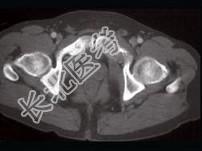

- 单项选择题男,59岁, 右侧髋骶部持续性疼痛,夜间加重, 2月前被确诊为肾细胞癌,结合图像, 最可能的诊断是 ( )

D、骨转移瘤